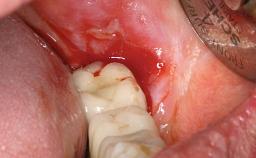

A 77-year-old male patient was referred for the management of frequent and repeated acrylic fracture of his existing mandibular fixed full-arch implant-supported metal/acrylic prosthesis. He also complained about softtissue soreness and the lack of retention and stability of his maxillary removable partial metal/acrylic prosthesis. Both prostheses had been delivered two years previously as part of his full-mouth rehabilitation (caries, tooth wear, tooth fracture). His medical history revealed high blood pressure, controlled with the use of antihypertensive medication.

Periodontal Status History of periodontitis or genetic predisposition